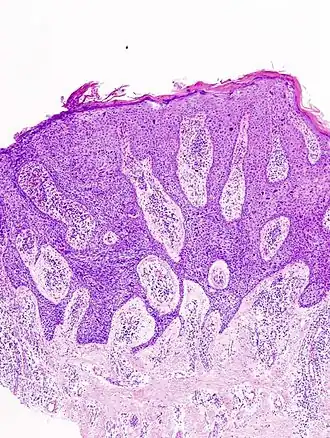

![]() Болезнь Боуэна под микроскопом | |

При заболевании на коже возникают солитарные либо в трети случаев множественные очаги: вначале это небольшое красное пятно или бляшка неправильной либо округлой формы с шелушением. Такие бляшки образуются при слиянии красноватых папул и узлов. Белые или жёлтые чешуйки на бляшке легко удаляются, под ними обнаруживается красная мокнущая поверхность. Бляшка чётко отграничена от окружающих тканей, постепенно растёт и со временем возвышается над уровнем кожи. Бляшка имеет пёстрый вид вследствие появления зон атрофии, гиперкератоза, разрастаний. В ряде случаев при болезни Боуэна возникают несколько постепенно сливающихся очагов. Постепенно процесс распространяется на весь слой эпидермиса. Со временем разрастающиеся очаги трансформируются в плоскоклеточный рак, что позволяет говорить о болезни Боуэна как о предраке.